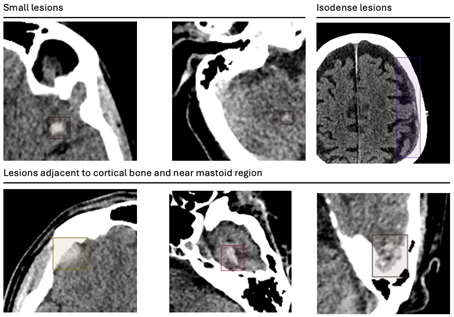

L’analyse des discordances a montré des profils d’erreurs similaires entre les deux cohortes et les études précédentes. Les faux négatifs concernaient principalement des lésions de petite taille (< 10 mm), des hémorragies isodenses ou des localisations proches de la base du crâne (voir image 3). Les faux positifs étaient liés à des tumeurs intra-axiales, des calcifications, des artefacts ou des structures anatomiques normales telles que la faux du cerveau, la tente du cervelet ou les sinus veineux (voir image 4).

Image3 clotide ruesh.png

Image 3 :  Exemples de faux négatifs pour les deux cohortes.